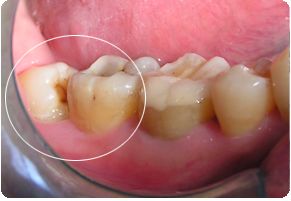

智齿又称智慧齿,是成年后一种常见的多生牙,虽说是智慧的象征,但临床上智齿发炎、肿痛及患冠周炎、龋齿的现象很普遍,所以拔牙治疗的人也不胜枚举,但由于智齿不同于一般患牙,不是随便拔了就了事了,这些关于拔智齿前后的注意事项你知道吗?下面就给大家详细介绍一下。

拔牙操作是一项严谨专业的外科手术,尤其是拔智齿,对于阻生、低位等拔牙难度大的智齿来说,既然是手术,术中或术后就会出现不同程度的出血、疼痛甚至感染等现象,所以术前工作要准备妥当,熟悉拔牙前后注意事项并严格遵守。